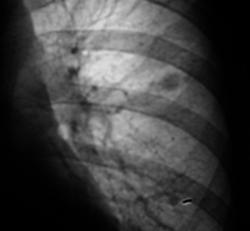

102._Rasshifrovka..jpg

А ещё смущает некоторое неоднородность, даже какие то плотные включения, межет это конечно сосуды накладываются.  Валентин Львович, у Вас же наверное где то томограмка завалялась?

Кстати, а такое образование ещё может соответствовать сосудистой мальформации, другое дело, что если раньше этого небыло. А если сравнивать от 2008г. так без динамики.